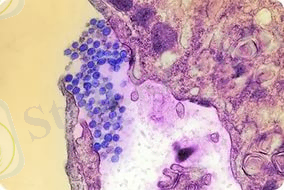

Гемморагиялық стафилококк

Бұл көптеген жедел жұқпалы аурулар тобы, осыларды біріктіретіні вирусты этиологиялығы, табиғи ошақтығы, айқын капиллярдың эндотелиінің зақымдалуы, геморрагиялық синдромының дамуы.

Вирус денеге кене шаққанда тері арқылы түседі. Вирустың тропизмдік қасиеті гипоталамикалық ортаға және вазотроптік (зақымдайды бүйрек, бауыр және ОЖЖ ұсақ тамырларының эндотелиін) . Осының нәтижесінде қантамырлардың өткізгіштігі жоғарылайды, қанның ұю жүйесінің қызметі бұзылады «ТІШҚҰң- дамиды. Сонымен қатар сүйек миының клеткаларының өсуі басылады, бауырдың функциясы бұзылады.